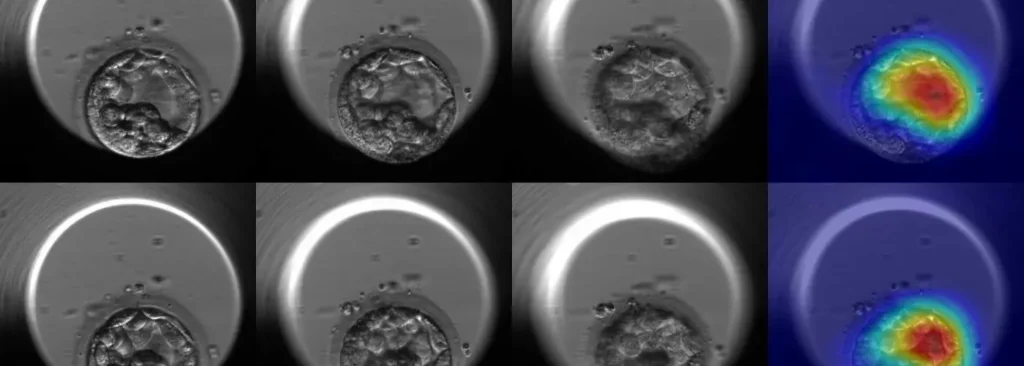

Las herramientas VIOLET™, MAGENTA™ y ROSE™ se basan en un modelo predictivo que evalúa la probabilidad de que un óvulo alcance el estadio de blastocisto, etapa clave en el desarrollo embrionario. Cada sistema está orientado a una instancia específica del tratamiento: VIOLET™ para pacientes que congelan óvulos, MAGENTA™ para ciclos de fecundación in vitro (FIV), y ROSE™ para procesos de donación ovocitaria.

“La calidad y el potencial de cada óvulo pueden medirse con mayor precisión, lo que permite planificar mejor los tratamientos y reducir los tiempos de espera”, señaló Marconetto. Además, estas herramientas aportan transparencia y respaldo en la toma de decisiones tanto para profesionales como para pacientes.